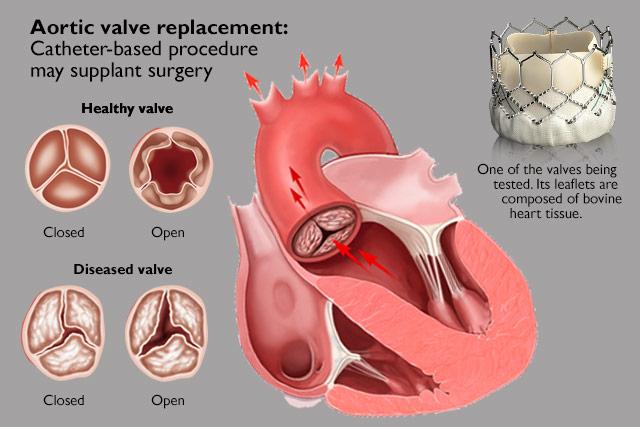

Value added benefits of the Aortic Valve Replacement:

Ø Doctor consultation charges

Ø Lab tests and diagnostic charges

Ø Room charges inside hospital during the procedure

Ø Surgeon Fee

Ø Nursing charges

Ø Hospital surgery suite charges

Ø Anesthesia charges

Ø Routine medicines and routine consumables (bandages, dressings etc.)

Ø Food and Beverages inside hospital stay for patient and one attendant.

Extra benefits:

ü Interpreter

ü Visa assistance

Ø Site tourism of the city

Ø Follow up with the doctor

Ø Airport pick up and drop

Ø Free online consultation with the doctor

Ø Priority appointments with the doctor

Ø Room upgrade from sharing to private